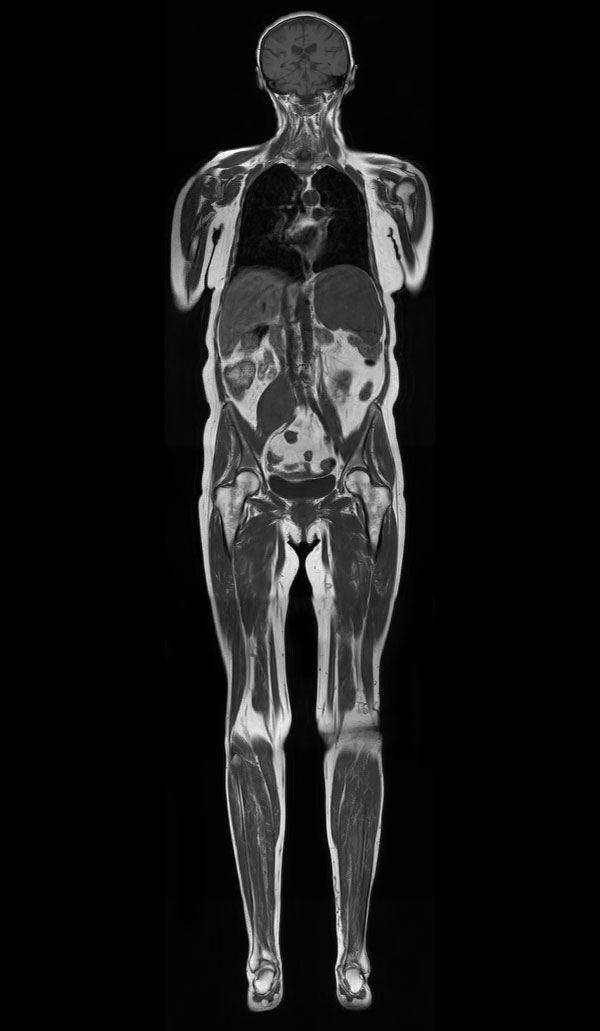

T1w TSE